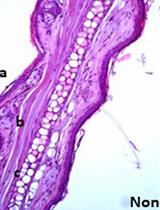

Transfusion-related acute lung injury (TRALI) is defined as acute lung injury that occurs within 6 hours of a blood product transfusion. TRALI continues to be a leading cause of transfusion-related mortality and we have developed a mouse model of TRALI to better understand the mechanisms by which injury occurs and to test therapeutic approaches. Our model is a two-event model based on immune priming and the challenge of BALB/c wild-type mice with cognate MHC Class I monoclonal antibody (MHC I mAb). Immune priming with LPS mimics the primed state of recipients (first event) that is important for the development of TRALI. Donor HLA antibodies are frequently implicated in TRALI reactions, and cognate MHC Class I antibody (second event) produces acute lung injury in primed animals. Here, we describe a detailed protocol with high reproducibility within animals.